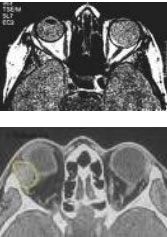

Además, la TAC es una herramienta de gran utilidad en la valoración de la orbitopatía tiroidea ya que nos permite visualizar las estructuras óseas y musculares de cara a planear el acto quirúrgico. En la TAC de los sujetos con enfermedad tiroidea, los músculos aparecen ensanchados. Este engrosamiento muscular reduce el volumen orbitario y puede comprimir el nervio óptico.

La valoración de la órbita se hace en los planos axial y coronal mediante cortes de 3 mm; si necesitamos evaluar el nervio óptico los cortes más apropiados son los de 1mm.